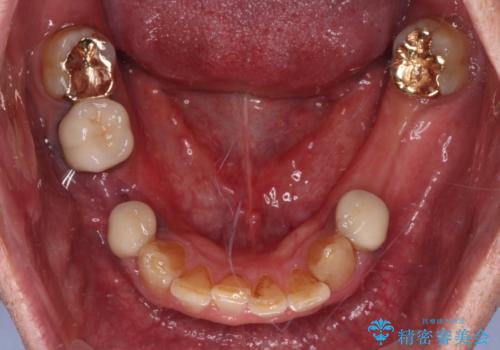

- 下顎両側の欠損と上顎前歯のデコボコを気にして来院された患者様です。

デコボコは今まで気にせずにいたそうですが、奥歯の欠損改善を機に、矯正治療に興味があるので、相談したいとのことでした。

奥歯に欠損が多く、矯正治療はやや難航することが予想されますが、患者様の希望もあり、上顎左右小臼歯を1本ずつ抜歯し、ワイヤー装置にて矯正治療を行うこととしました。